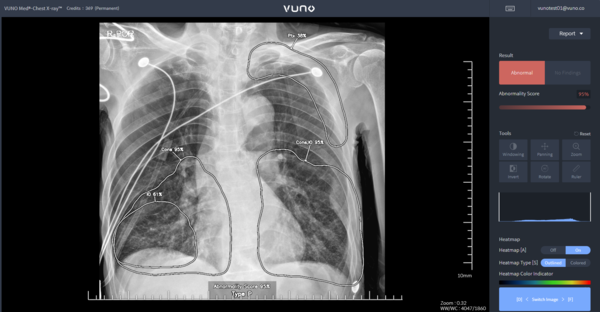

[서울와이어 정윤식 기자] 뷰노는 AI 기반 흉부 X-ray 판독 및 소견 검출 의료기기 VUNO Med-Chest X-ray(이하 Chest X-ray)가 6월 1일부터 비급여 시장 진입이 가능해졌다고 15일 밝혔다.

뷰노에 따르면 Chest X-ray는 안전성과 진료 현장에서의 잠재적 유용성을 인정받은 의료 AI 솔루션이다. 이 제품은 보건복지부의 혁신의료기술 관련 고시 확정에 따라 오는 6월 1일부터 2028년 5월 31일까지 3년간 임상 현장에서 사용이 가능해졌다.

Chest X-ray는 흉부 X-ray 영상을 분석해 5개의 이상 소견(결절, 경화, 간질성 음영, 흉막 삼출, 기흉) 유무를 검출하고 소견 조합을 통해 2개 질환(폐렴, 폐결핵)을 선별하는 진단 보조 소프트웨어이다.